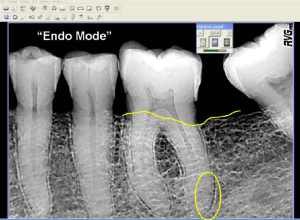

| This is the same x-ray in "endo" mode. (Screen shots courtesy of Allan G. Farman). |